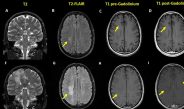

• Penelitian Neuroimaging Memastikan Perlindungan Kognitif yang Diberikan oleh ART yang Efektif

Penelitian Neuroimaging Memastikan Perlindungan Kognitif yang Diberikan oleh ART yang Efektif

Neuroimaging Study Affirms Cognitive Protections Conferred by Effective ART Penelitian terbaru yang terperinci menunjukkan salah satu bukti ilmiah terkuat yang kita miliki sejauh ini

Maret 13, 2026 admin 0